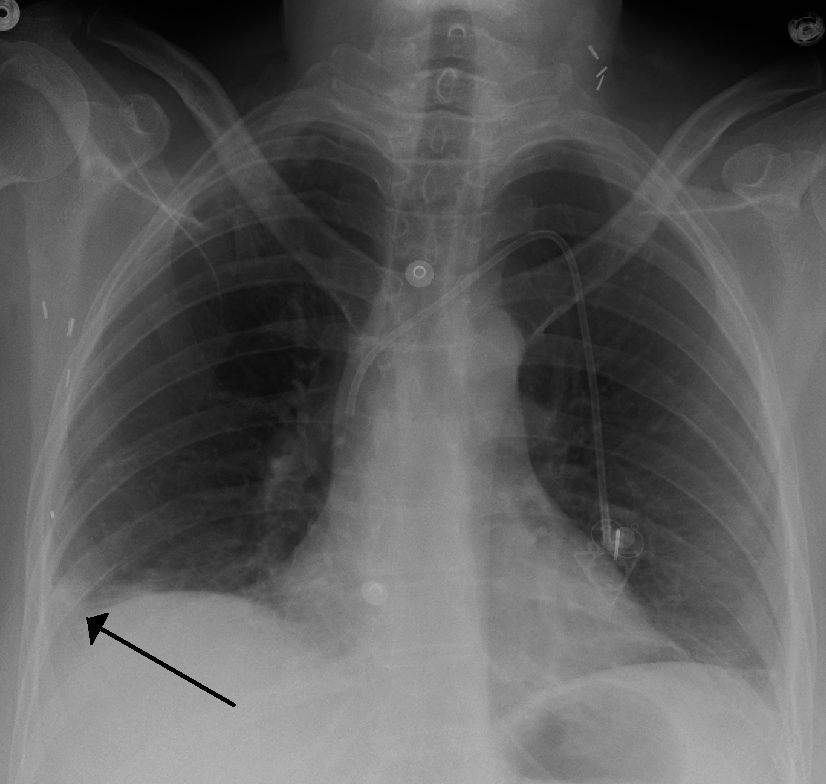

PE 진단에 자주 시행되지만 민감도가 낮은 검사로는 흉부 X선, 다리 초음파 검사등이 있다.

• 흉부 X-선: 숨가쁨 환자의 다른 원인(울혈성 심부전, 늑골 골절 등) 배제를 위해 시행.

폐색전증 환자의 햄프턴 혹

• 흉부 X-선: 숨가쁨 환자의 다른 원인(울혈성 심부전, 늑골 골절 등) 배제를 위해 시행. PE 흉부 X-선은 드물게 정상 소견을 보이며,[65] 징후(웨스터마크 징후, 햄프턴 융기)도 부족하다.